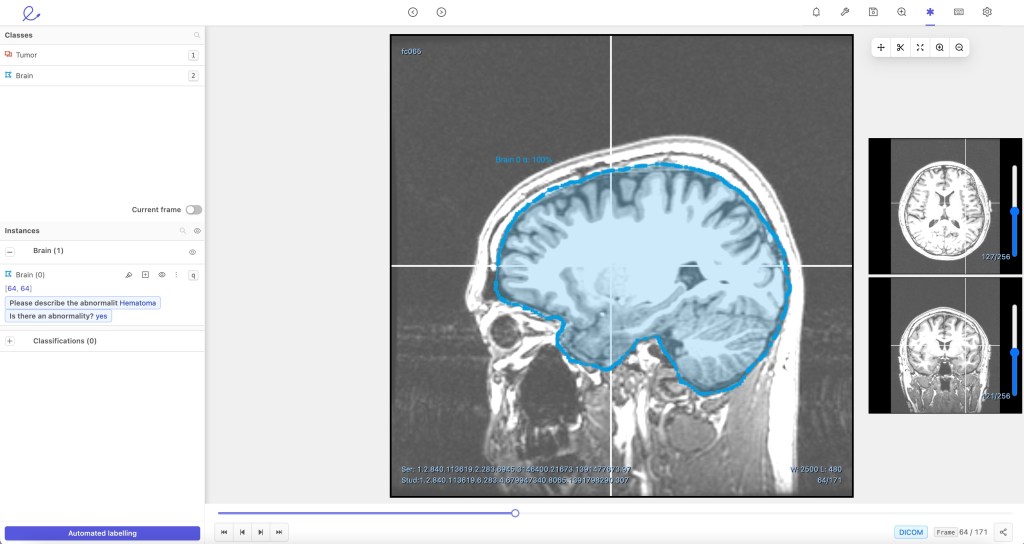

Encord has developed a set of tools that allow radiologists to zoom in on DICOM images, a format universally used to transmit medical images. And instead of having a radiologist sit down and annotate an entire image, the software is designed to ensure that only key portions of the image are labeled.

To create a labeled data set, more than one doctor will literally go through the images one by one, drawing polygons around relevant features. Other times, it can be done with open source tools or sensors. But either way, scientific literature suggests this step is a major bottleneck in the healthcare AI world, especially when it comes to radiology, which is one area where AI has been predicted to make major strides, but has largely failed to deliver any major paradigm shifts.

CordVision, basically, is a version of an active learning process called micro-modeling. That technique, broadly, works by having a team label a small, representative sample of the images. Then a specific AI is trained on those images and then applied to the wider pool, which the AI labels. Then human reviewers can check the AI’s work as opposed to doing the labeling from scratch.